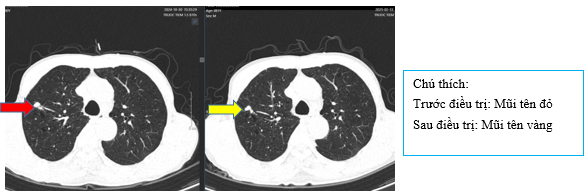

Hình 5: Hình ảnh nốt đặc thùy trên phổi phải trước điều trị kích thước ~9mm, sau điều trị đạt duy trì bệnh ~9mm

Hình 6: Hình ảnh nốt đặc thùy trên phổi trái trước điều trị ~3mm và sau điều trị kích thước ~5mm